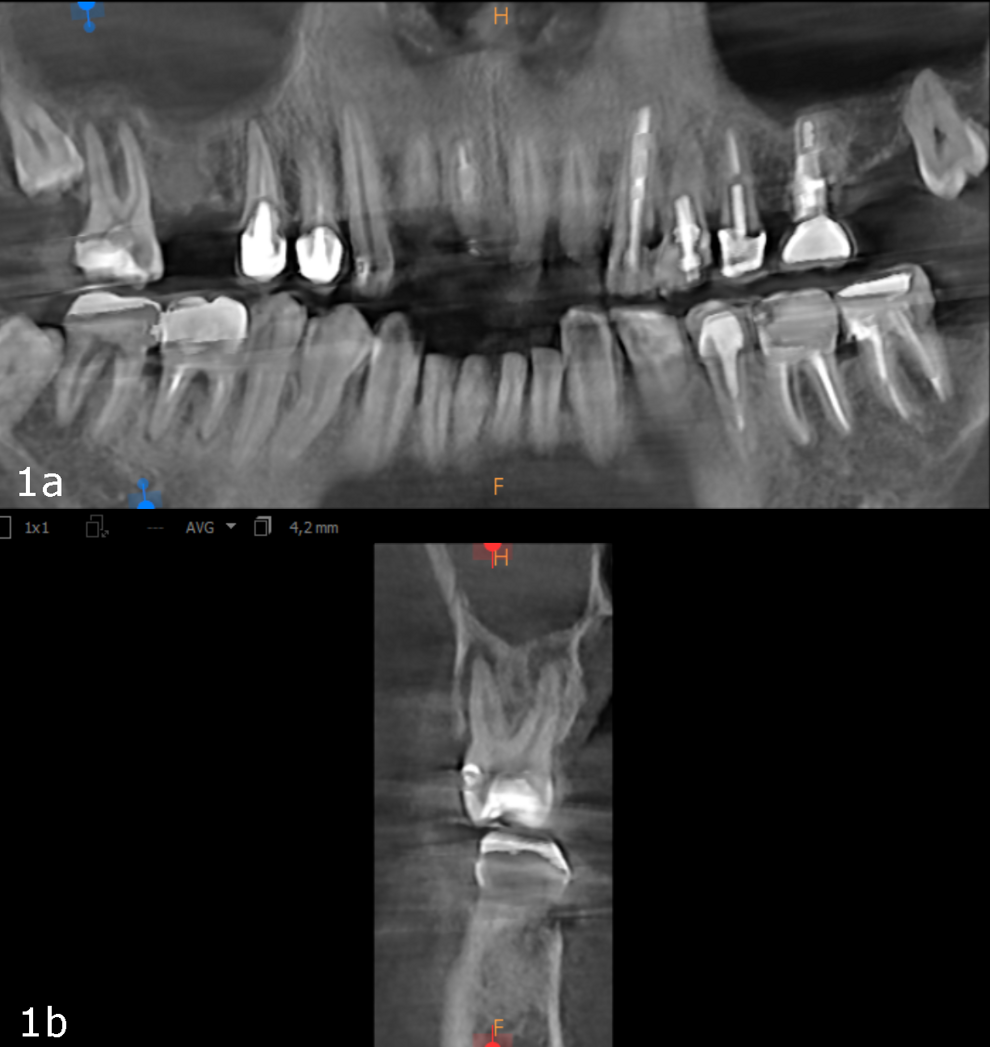

Figs. 1a & b: Initial small-volume CBCT scan, panoramic view (a) and cross-section of tooth #17 (b).

The 61-year-old male patient wanted to have his missing maxillary right teeth replaced with implants. After examination by an implantologist, he was referred to our dental office for further dental treatment because of the findings of a small-volume CBCT scan taken: advanced inflammation and bone loss were visible in the periodontal tissue of the maxillary right second molar and severe maxillary sinusitis was observed (Figs. 1a & b).

Figs. 10a & b: CBCT scan taken 12 weeks later showing complete healing, panoramic view (a) and cross-section of tooth #17 (b).

As a follow-up, we took a CBCT scan 12 weeks after the obturation, and it clearly showed that both the periapical tissue as well as the paranasal sinuses had recovered fully (Fig. 7). Newly formed cortical and cancellous bone was visible around the buccal and palatal roots (Figs. 8a & b) and extended in the caudal direction. Furthermore, all the paranasal sinuses were clear, and no epithelial widening was visible (Figs. 9a-f).

The bottom line is that it is really essential to locate the origin of our patients’ problem and evaluate its consequences to give proper treatment that facilitates complete regeneration of not only the periapical area but also the entire area of the paranasal sinuses (Figs. 10a & b). This can help the body and the immune system to achieve miraculous healing with a non-invasive treatment protocol.